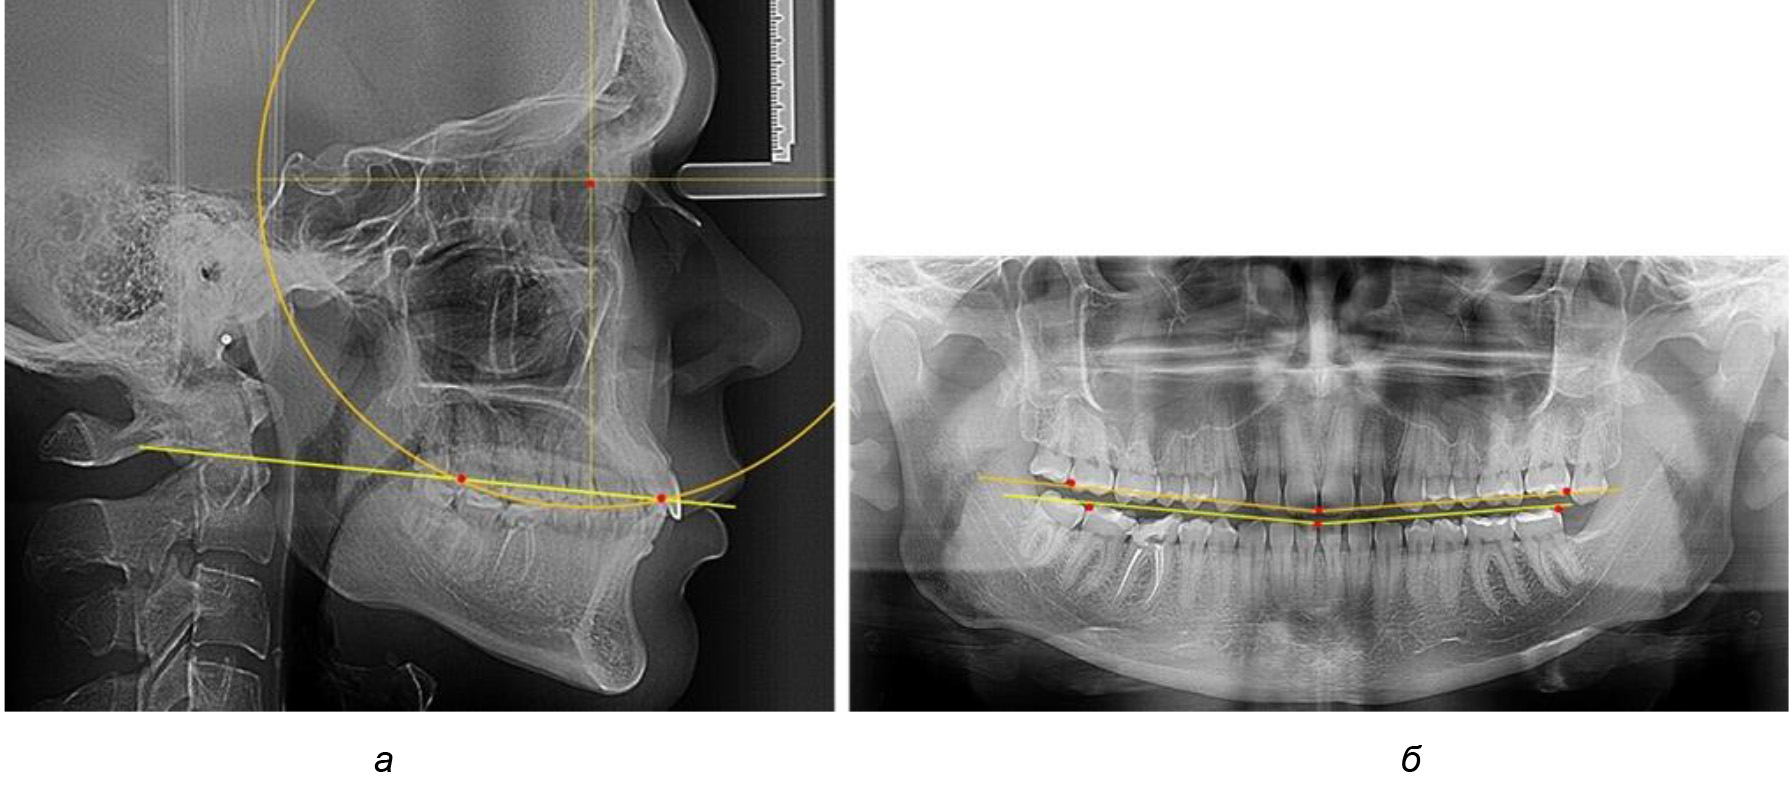

Рис. 2. Особенности кривой Spee на ТРГ (а) и ОПТГ (б) у людей с признаками вертикального роста

На рентгенограммах людей 2-й подгруппы (30 человек с нейтральным типом роста) величина угла нижней челюсти в среднем составила (120,34 ± 2,19) ° и характеризовала нейтральный тип нижней челюсти.

Глубина кривой Spee в среднем по 2-й подгруппе составил (3,54 ± 0,58) мм, что было незначительно меньше, чем при анализе аналогичного показателя 1-й подгруппы.

Достоверных различий с показателями, полученными при анализе ТРГ и ОПТГ, нами не отмечено (р ˃ 0,05). Деление величины радиуса круга к длине окклюзионной линии составило 1,612 ± 0,02, что, так же как и в 1-й подгруппе, было близким по значению к числу Фибоначчи (1, 618).

В 3-ю подгруппу вошли ТРГ и ОПТГ 14 человек 1-й группы, что составило (22,58 ± 5,31) % от общего количества людей 1-й группы. Величина угла нижней челюсти в среднем составила (114,85 ± 2,87)° и характеризовала горизонтальный тип нижней челюсти.

Глубина кривой Spee в среднем по 2-й подгруппе составил (2,94 ± 0,47) мм, что было меньше, чем в других подгруппах. Деление величины радиуса круга к длине окклюзионной линии составило 1,616 ± 0,02 (рис. 4).

Рис. 3. Особенности кривой Spee на ТРГ (а) и ОПТГ (б) при нейтральном типе роста нижней челюсти

Рис. 4. Особенности кривой Spee на ТРГ (а) и ОПТГ (б) у людей с горизонтальным типом лица